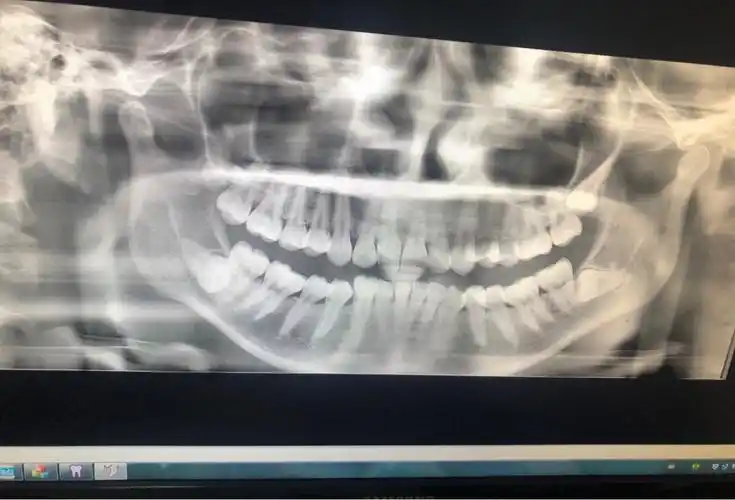

看过牙的朋友都知道,牙医经常说或者在病历里写16(右上6),21有问题

看牙医是如何用符号表示不同的牙齿的

00去看牙医总是听医生会说到牙位的数字号码00那今天小研就给小